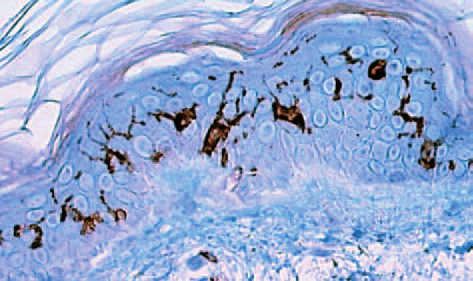

Al igual que los melanocitos, que son responsables de la pigmentación de la piel, las células de Langerhans no forman uniones desmosómicas con los queratinocitos circundantes. Esto implica que mantienen una relación diferente con la matriz celular, lo que podría influir en su función y en su capacidad para interactuar con el entorno. En los cortes histológicos convencionales, el núcleo de las células de Langerhans se tiñe intensamente con hematoxilina, lo que resalta su prominencia en comparación con otras estructuras celulares. El citoplasma, en contraste, aparece más claro, lo que añade dificultad a su identificación sin técnicas adicionales.

Para abordar esta limitación, se han desarrollado métodos especiales que permiten visualizar las células de Langerhans con mayor claridad. La impregnación con cloruro de oro y la inmunotinción utilizando anticuerpos dirigidos contra moléculas como CD1a son ejemplos de estas técnicas que destacan su presencia en el estrato espinoso de la epidermis. A través de estas metodologías, se pueden observar las prolongaciones dendríticas de las células de Langerhans, que son similares a las del melanocito, lo que sugiere una especialización funcional en la comunicación con otras células del sistema inmunológico y el entorno cutáneo.